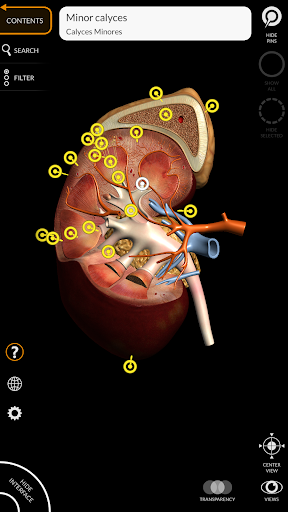

"Anatomy 3D Atlas" cho phép bạn nghiên cứu giải phẫu người theo cách dễ dàng và tương tác.

Thông qua giao diện đơn giản và trực quan, bạn có thể quan sát mọi cấu trúc giải phẫu từ mọi góc độ.

Các mô hình giải phẫu 3D đặc biệt chi tiết và có kết cấu lên đến độ phân giải 4k.

Việc phân chia theo vùng và chế độ xem được xác định trước giúp quan sát và nghiên cứu các bộ phận hoặc nhóm hệ thống riêng lẻ và mối quan hệ giữa các cơ quan khác nhau.

MÔ HÌNH GIẢI PHẪU 3D

• Hệ thống tiêu hóa • Hệ thống tiết niệu sinh

dục (nam và nữ)